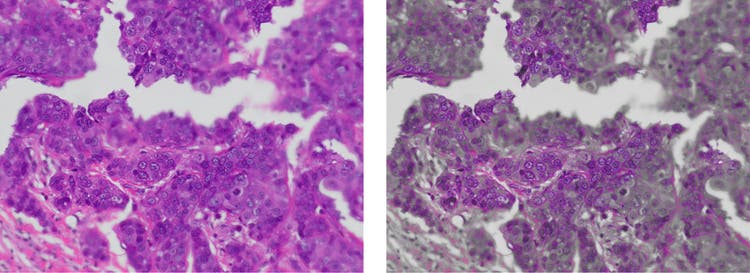

Noise reduction using image averaging in digital microscope cameras

Without OSIA (left) vs. with OSIA (right)